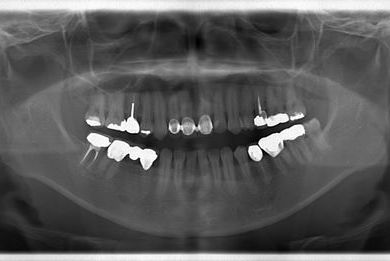

治療内容 メタルボンドセラミック(クラウン1本、ブリッジ3本、メタルボンドセラミック土台1本)+ハイブリッドセラミックインレー1本

治療部位

4

7 6 5 4